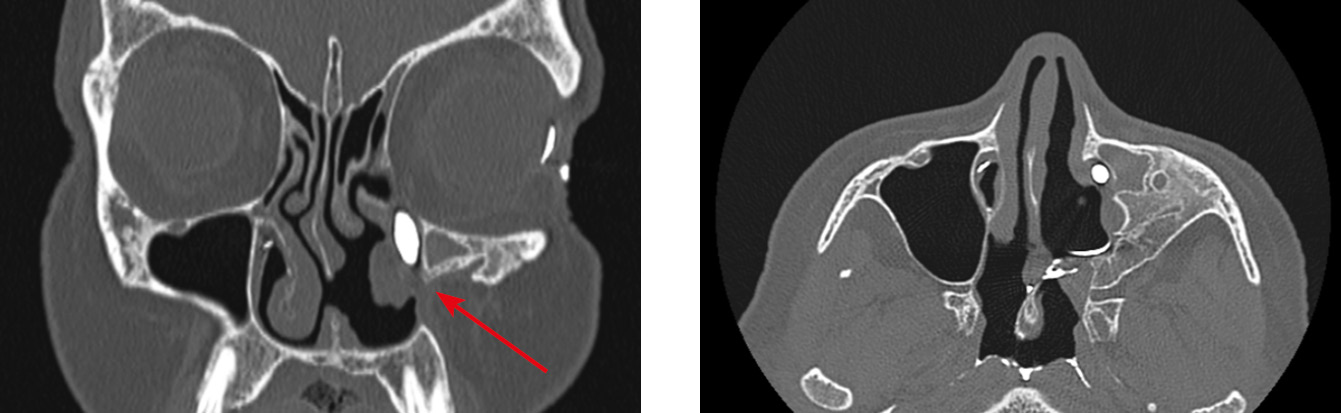

Облитерация СОП на уровне нижней трети НСК возникала также у пациентов после таких хирургических вмешательств, как различные виды конхопластик нижних носовых раковин (6 случаев). В двух случаях облитерация устья НСП сформировалась после выкраивания лоскутов в области нижнего носового хода: с целью пластического закрытия перфорации перегородки носа (1 случай, рис. 5), а также при проведении инфратурбинальной антростомии (1 случай, рис. 6). По данным МСКТ костная часть НСК у этих пациентов оставалась интактной. При планировании вмешательства в нижнем носовом ходе целесообразно определить локализацию устья НСП, во избежание его травматизации. В случаях недостаточной визуализации устья НСП возможна его идентификация при промывании СОП, в том числе с использованием красителя [25].

Рис. 5. Случай неудачной попытки пластики перфорации перегородки носа. Развитие вторичного дакриоцистита с частичной проходимостью носослезного протока (OS) после забора лоскута слизистой оболочки в области нижнего носового хода слева, формирование дакриостеноза на уровне устья носослезного протока (стрелка)

Fig. 5. A case of plasty failure for nasal septal perforation. Secondary dacryocystitis with partial patency of the nasolacrimal duct (OS) after dissection of a mucosal flap in the left inferior nasal passage, dacryostenosis at the level of the nasolacrimal orifice (arrow)

Рис. 6. Хронический дакриоцистит (OD) с частичной проходимостью носослезного протока после гайморотомии, дакриостеноз носослезного канала на уровне нижней трети (стрелки)

Fig. 6. Chronic dacryocystitis (OD) with partial patency of the nasolacrimal duct after maxillary sinusotomy, dacryostenosis of the nasolacrimal duct at the level of the lower third (arrows)